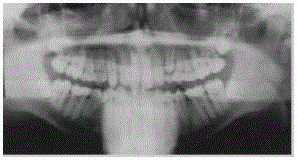

Enunciado 1881475-1

Oral Surgery, Oral Medicine, Oral Pathology, set./1999.

Com relação aos achados radiográficos presentes na situação clínica ilustrada na figura acima, assinale a opção correta.